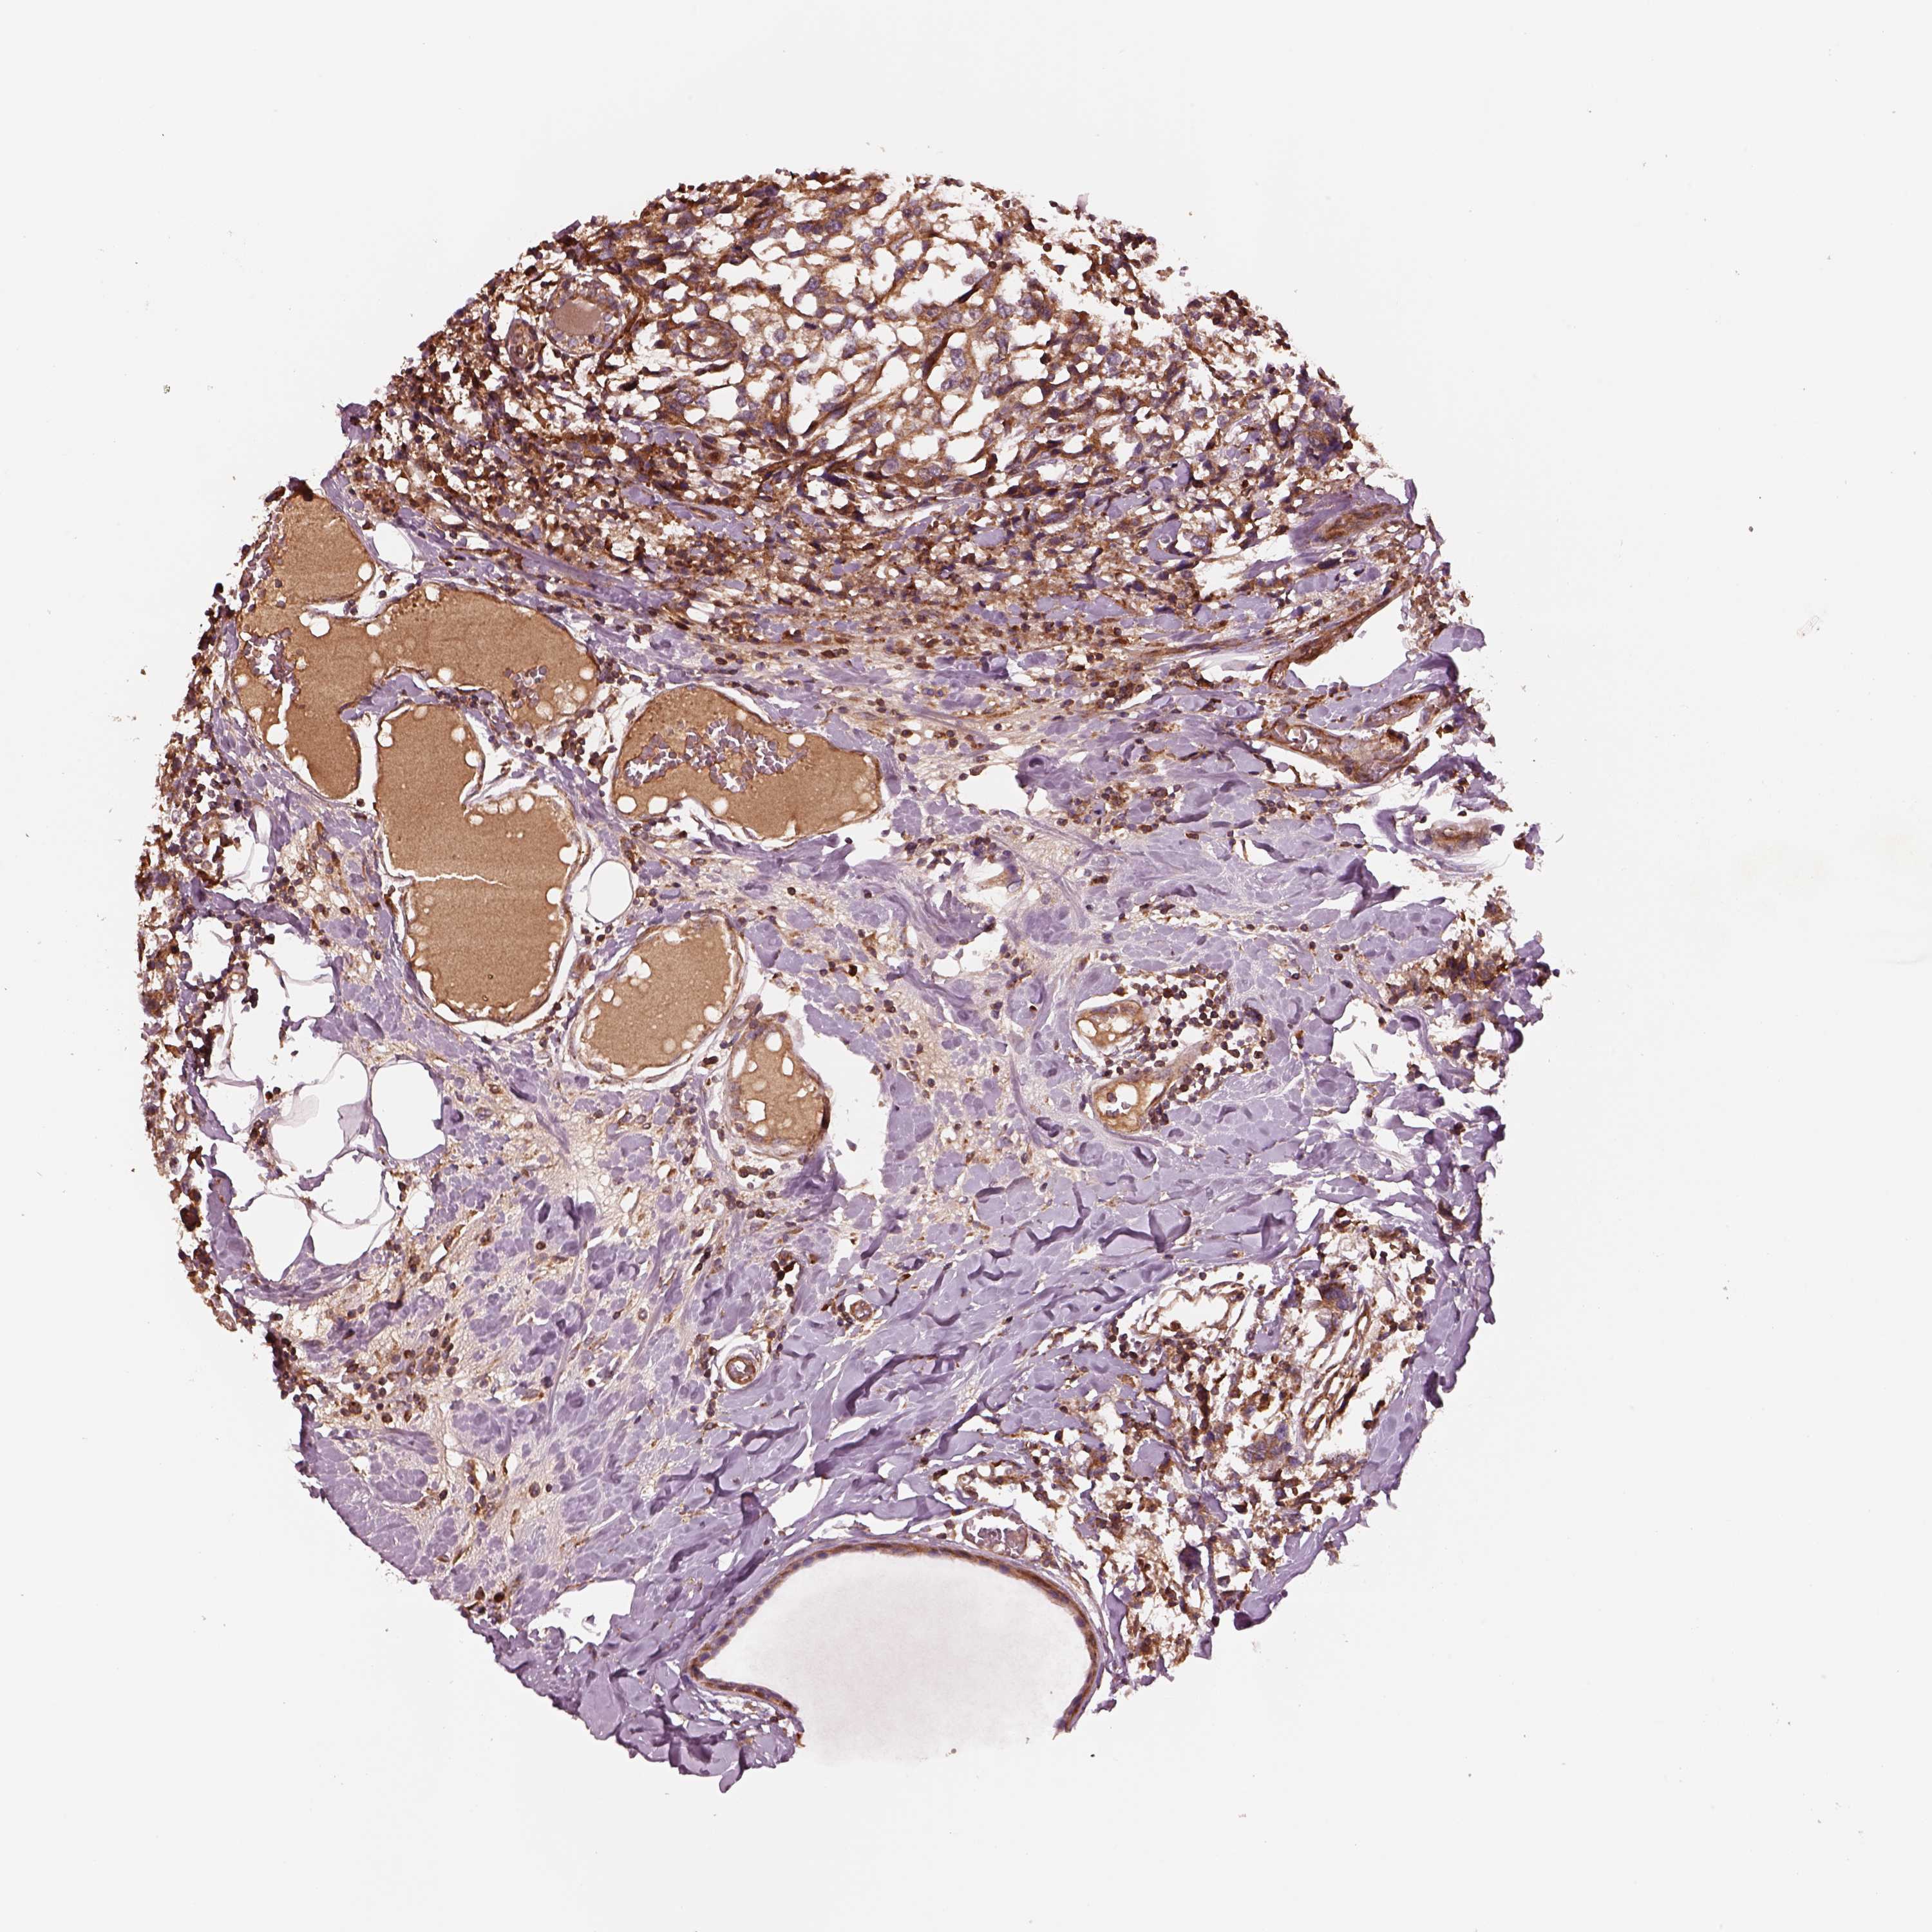

CANCER BREAST CANCER Show tissue menu

BRCA TCGA BRCA VALIDATION PROTEIN EXPRESSION